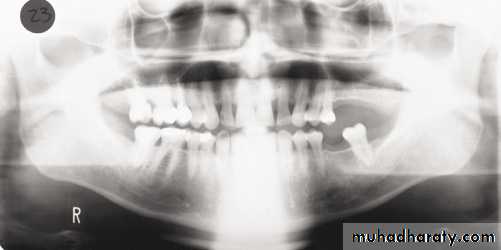

1, Mandibular condyle. 2, Articular eminence. 3, Coronoid process of mandible superimposed on zygomatic arch. 4, Posterior wall of maxillary sinus. 5, Posterior wall of zygomatic process of maxilla. 6, Hard palate. 7, Nasal septum. 8, Tip of nose. 9, Dorsum of tongue. 10, Hyoid superimposed over inferior border of mandible. 11, Inferior border of maxillary sinus. 12, Image of cervical spine. 13, Medial border of maxillary sinus. 14, Infraorbital canal. 15, Infraorbital rim. 16, Pterygomaxillary fissure. 17, Anterior border of the pterygoid plates. 18, Lateral pterygoid plate superimposed over soft palate and coronoid process of mandible. 19, Ear lobe. 20, Inferior border of mandibular canal. 21, Mental foramen. 22, Posterior wall of nasopharynx. 23, Inferior border of mandible superimposed from opposite side. 24, Soft palate over mandibular foramen of mandible.